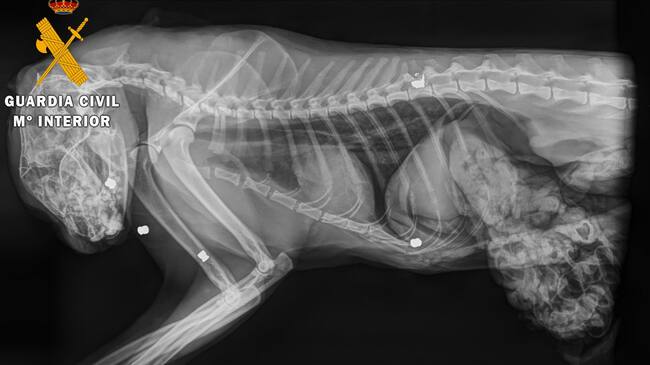

Al cuerpo del gato se le realizó una necropsia en una clínica veterinaria de Estella, donde se determinó que el animal había fallecido por el impacto de cinco perdigones. Se extrajo uno de los cinco proyectiles por si fuese necesario para un análisis. Agentes del Servicio de Protección de la Naturaleza Seprona iniciaron una investigación en la zona, gracias a la cual se intervino una carabina de aire comprimido de calibre 4,5 mm a un vecino de la localidad, del que los agentes tenían sospechas de que pudiese ser el autor de los hechos.

El proyectil y el arma fueron remitidos al laboratorio de criminalística de la 10ª Zona de la Guardia Civil en La Rioja para la realización de los estudios balísticos. Finalmente, estos estudios establecieron que el proyectil encontrado en el cadáver del gato había sido disparado con el arma intervenida. Se procedió a investigar al dueño del arma como supuesto autor de un delito de maltrato de animal doméstico.